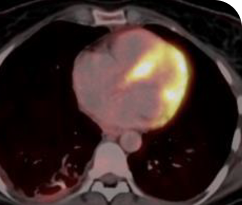

Response in primary and metastatic lesions1

Lung imaging of primary tumors.

SCAN 1: LUNG

SCAN 2: LUNG AND BONE

Images courtesy of Dr Maximilian Hochmair.

Response to VITRAKVI1

- Partial response and symptom improvement confirmed by chest X-rays after <1 month of treatment

- Imaging performed 6 weeks into treatment revealed considerable decrease in the size of both target lesions

- Complete clinical response achieved by 12 months with residual scarring